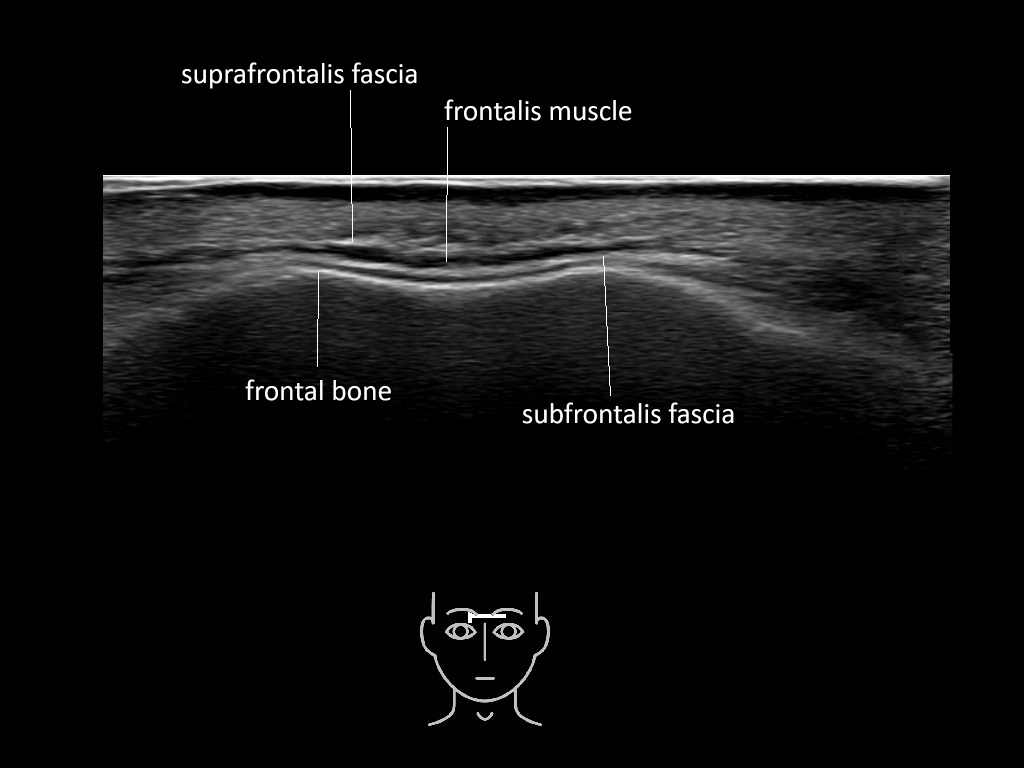

In this section you will learn more about the different layers of the face with the use of ultrasound. When you click on the secondary ultrasound image, you will see the different structures as an overlay. This will help to train yourself to recognize the different layers of the face.

Study the first image to recognize the different layers. If you are sure about the layers, swipe to the second image to view the answer (if applicable).